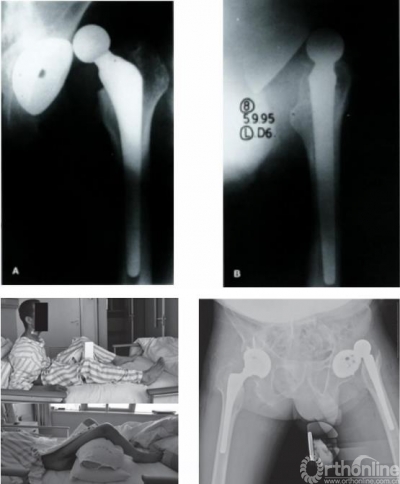

强直性脊柱炎对THA的影响

强直性脊柱炎(AS)患者脊柱矢状面的畸形,会导致胸椎后凸增大,腰椎前凸减小,这样的生理结构导致患者站立位骨盆出现过度后倾。系统综述也显示,这样的后倾导致髋臼前倾角异常增大。骨盆后倾,髋关节前倾角增大也是THA术后脱位和翻修的主要原因。因此针对AS患者,术前需要设计髋臼假体位置。

图7 AS引起THA术后脱位病例

手术时可根据后倾角度调整髋臼假体置入角度,减小外展与前倾角,防止术后脱位,增加站立位髋关节稳定性的同时,减少了假体与骨的接触面积,以适应变化的脊柱-骨盆力线,避免术后出现髋臼假体过度前倾,以及站立位时发生后方撞击、前方不稳甚至前脱位等并发症。对于合并脊柱后凸畸形的AS患者,除非畸形过于严重,应首选脊柱矫形术,再行THA。